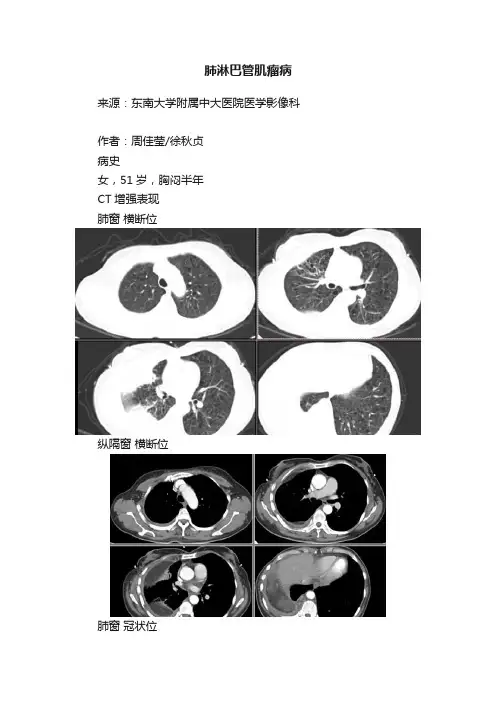

肺淋巴管肌瘤病来源:东南大学附属中大医院医学影像科作者:周佳莹/徐秋贞病史女,51岁,胸闷半年CT增强表现肺窗横断位纵隔窗横断位肺窗冠状位纵隔窗冠状位诊断结果示:肺淋巴管肌瘤病,右侧胸腔乳糜胸肺淋巴管肌瘤病:4、淋巴细胞间质性肺炎(LIP)最常见与Sjogren综合征(干燥综合征)相关,也可与AIDS、原发胆汁性肝硬化、淋巴结增生症及自身免疫性甲状腺疾病。